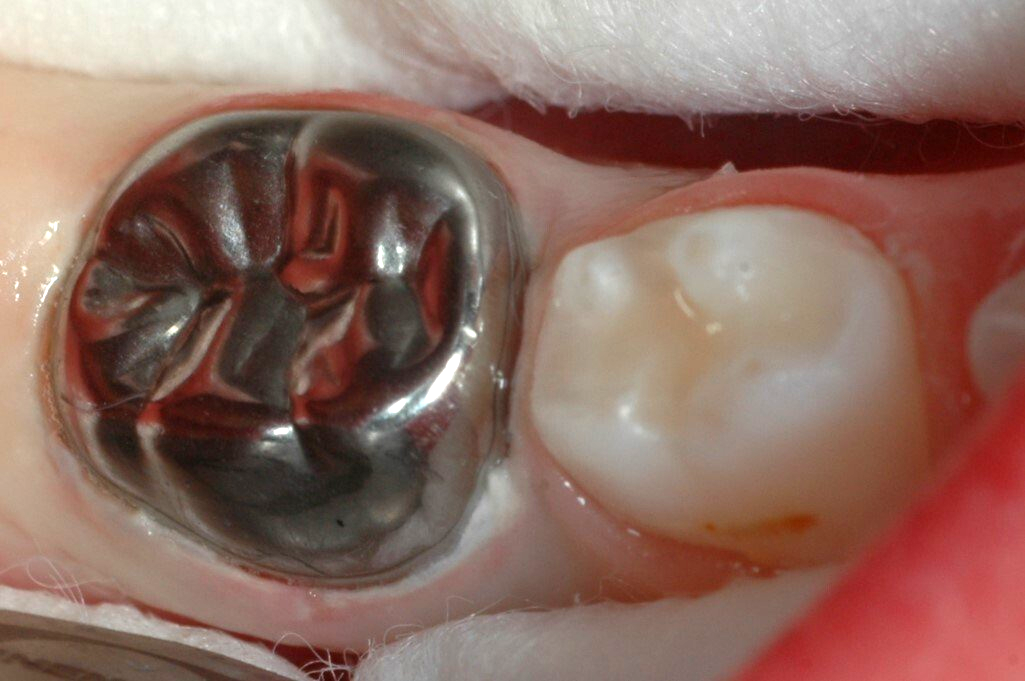

Backenzähne werden mit konfektionierten Edelstahlkronen überkront. Dies ist eine seit langem bewährte Methode zur Zahnerhaltung. Die Kronen sind extrem haltbar und sehr gut verträglich.

Hier haben wir einmal die Eingliederung einer Kinderkrone dokumentiert:

Schritt 6: Fertig zementierte Krone